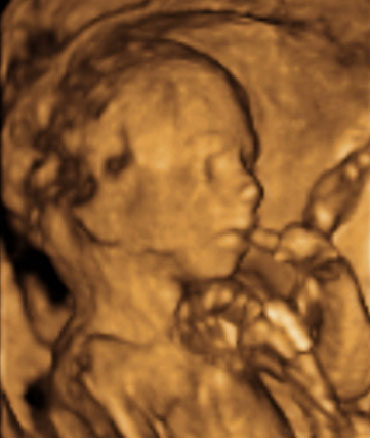

La imagen ecográfica en dos dimensiones es básica para obtener la imagen en 3D en tiempo casi real.

Ecografía Embarazo 2D y 3D - SEMANA 20

Ecografía Embarazo 4D - SEMANA 20